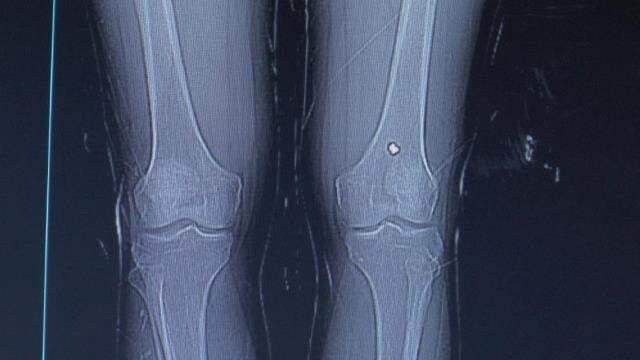

Nevşehir'de bacağından tüfekle vurulan şahıs, tedavisinin ardından taburcu edildi. Olaydan 13 gün sonra şikayetleri artınca tekrar hastaneye giden şahsın diz kapağında mermi olduğu anlaşıldı.

13 gün sonra diz kapağındaki ağrıların artmasıyla yeniden hastaneye müracaat eden Değerlier, burada hayatının şokunu yaşadı. Değerlier'in diz kapağında mermi olduğu anlaşıldı. Ortopedi polikliniğine sevk edilen şahsın diz kapağındaki mermi ameliyatla alındı.